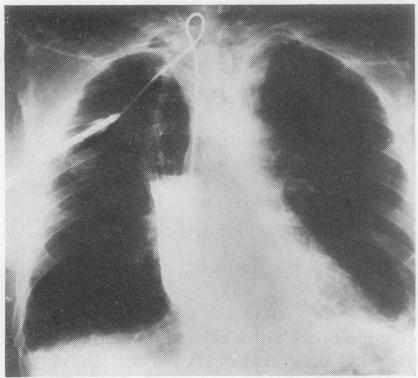

A technique of cervical gastrostomy is described. Cervical gastrostomy as an alternative to the use of an indwelling nasogastric tube after cervical oesophagogastrostomy after resection for cancer has been used in six patients and appears to have certain advantages in terms of effective gastric decompression, avoiding discomfort to the patient, and simplification of postoperative nursing. It may play a significant role in reducing postoperative mortality from aspiration pneumonitis and other pulmonary complications.

本文描述了一种颈部胃造口术的技术。颈部胃造口术可作为癌症切除术后颈部食管胃吻合术后使用留置鼻胃管的替代方法,已应用于6例患者,在有效胃减压、避免患者不适以及简化术后护理方面似乎具有一定优势。它可能在降低误吸性肺炎和其他肺部并发症导致的术后死亡率方面发挥重要作用。